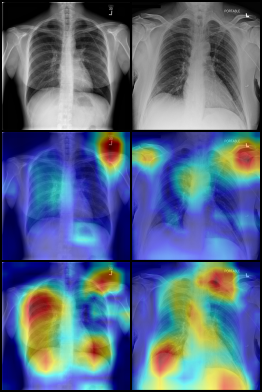

For the covid-qu-Ex dataset, we trained the network with hyperparameters λ=5𝜆5\lambda=5, ρ=0.25%𝜌percent0.25\rho=0.25\%, 2 downsampling steps in the attention network, and 5 downsampling steps in the replacement network. We used a learning rate of 21042superscript1042\cdot 10^{-4} for both the lens and classifier. As there is no validation set without shortcuts for covid-qu-Ex, we evaluated the effectiveness of the lens in identifying shortcuts using GradCAM [22]. Figure 4 shows the GradCAM images for all three classes and both trained networks. From these experiments, we made several observations. First, without the lens, the network predominantly focused on areas in the corners of the images, mostly in areas with text. Second, with the attention lens, the network focused on more relevant sections of the image, including the lungs. Our proposed approach not only explains shortcuts but also corrects them, as shown in Fig. 5, where highly localized shortcuts such as markers and text are removed.

Refer to caption

(a) Normal

(b) COVID

(c) Pneumonia

Figure 4: GradCAM images showing network attention when training on the covid-qu-Ex dataset. Row 1 is the input image from the validation set. Row 2 is the classifier attention of a network trained without, and Row 3 with our proposed model.